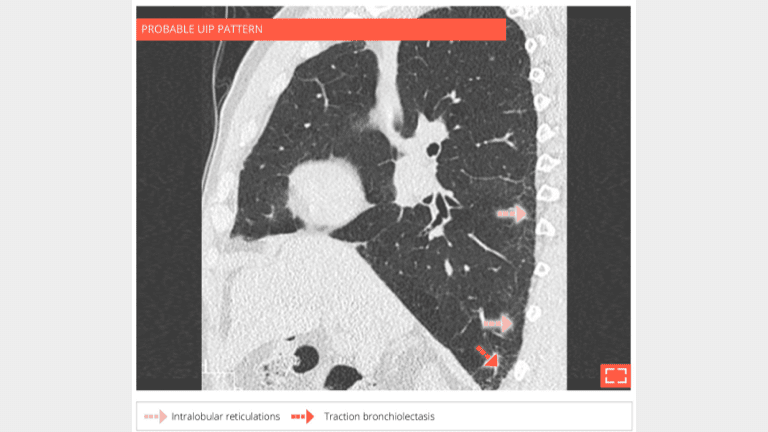

4. Intralobular reticulations

• Isolated and subtle subpleural intralobular reticulations.

• No ground-glass opacity or honeycombing or traction bronchectosis.